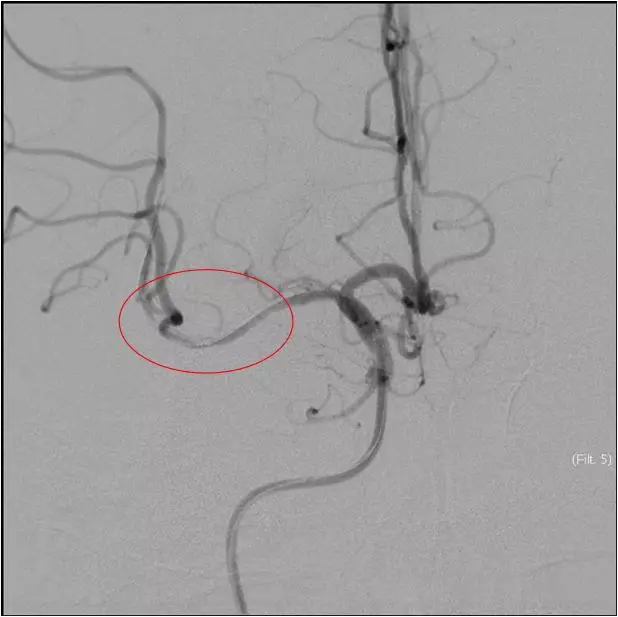

再次与家属沟通病情,交代支架植入风险,家属表示理解,准备支架解脱

5MIN后

再次观察10MIN后

16:30分

手术结束

持续替罗非班4ml/H静脉泵入